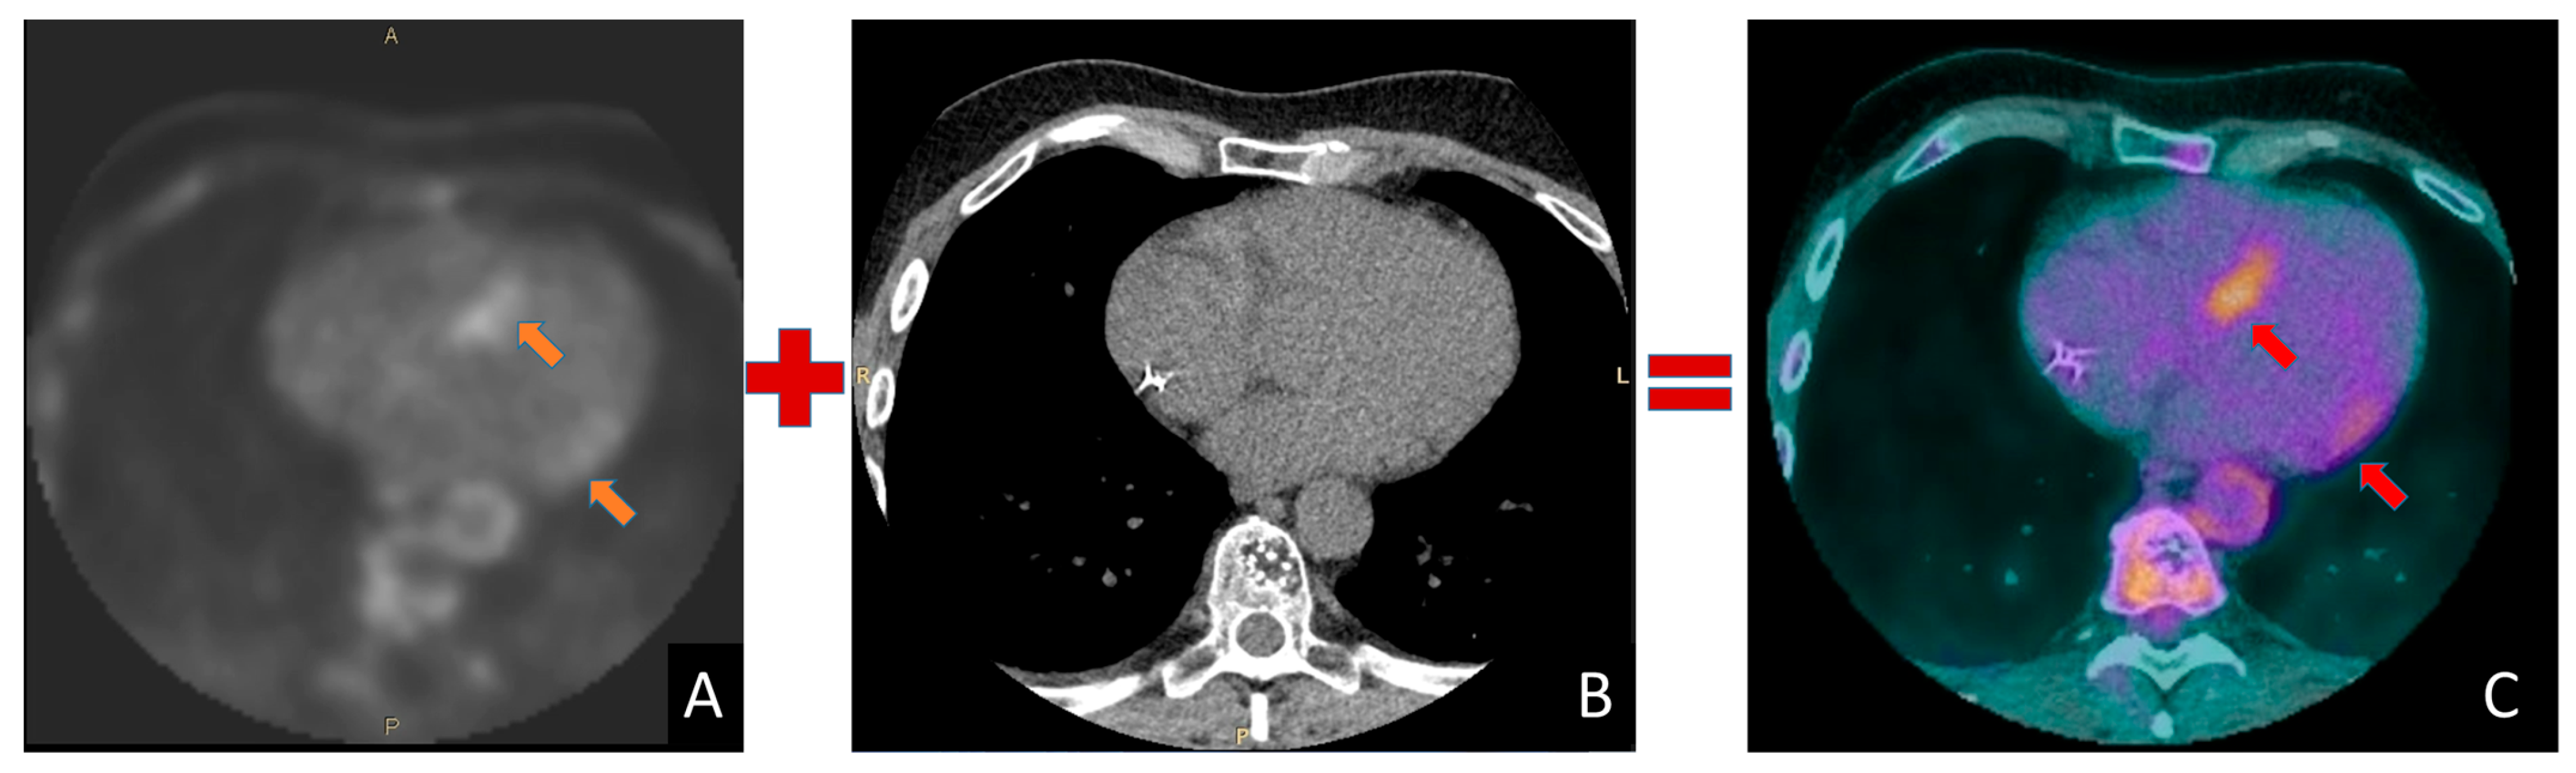

4.4. Athlete with Ventricular Arrhythmias and Late Enhancement on Cardiac MRI Suspected for Cardiac Sarcoidosis